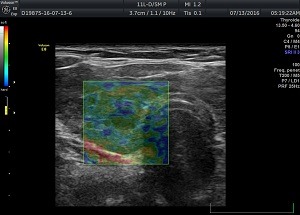

Обстеження проводиться за допомогою ультразвукового обладнання і спеціальних датчиків. На монітор лікарю виводиться еластограма, де різними кольорами позначається щільність тканин. Згідно шкали жорсткості кольорів та коефіцієнту strain ratio – що індивідуально розраховує контрольне значення деформації тканин, лікар робить опис і висновок.

За шкалою кольорів:

1.Синьо-зелений – тканини мають середню жорсткість, за подальшими змінами необхідно спостерігати або застосовувати додаткові методи діагностики (біопсія за показами).

2. Зелено-жовто-червоний колір – тканина низької жорсткості, що є показником доброякісного утворення.

3. Синій колір – є показником тканини високої жорсткості, що вказує на злоякісний характер утворення.